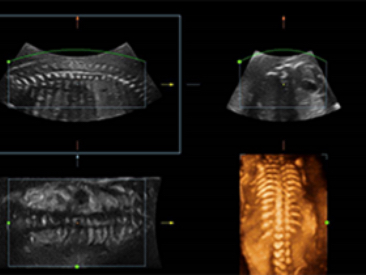

Klinik G?rĂŒntĂŒler